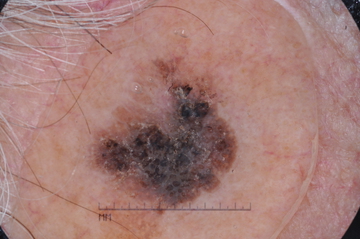

Case: 284